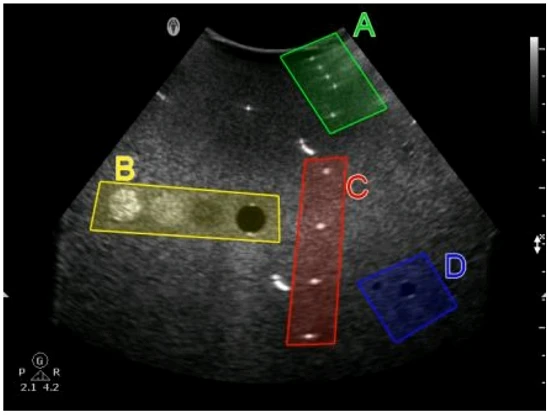

Which target group in this image of a tissue-mimicking phantom is used for gray-scale evaluation?

The suggested answer is B.